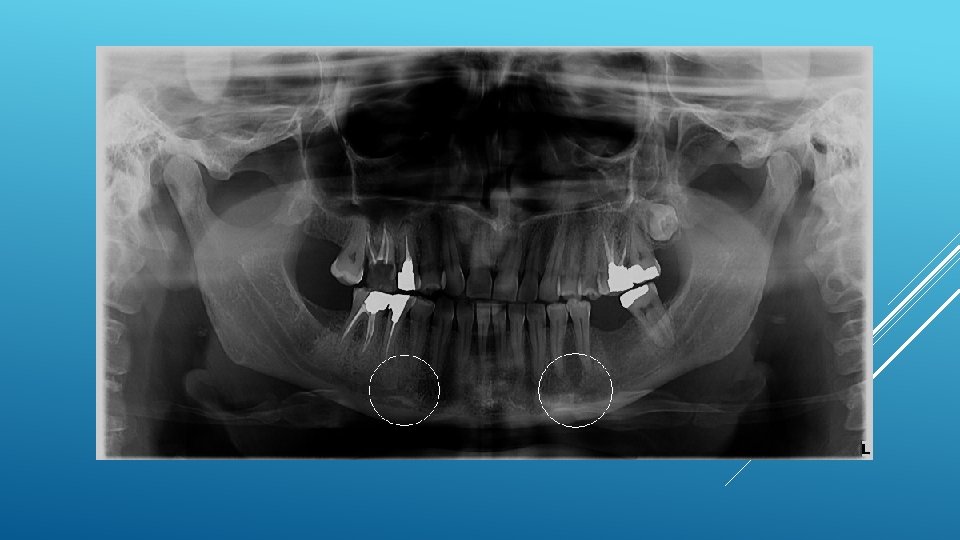

LOCATION AND DIMENSIONS OF THE MENTAL FORAMEN: A RADIOGRAPHIC ANALYSIS BY USING CONE-BEAM COMPUTED TOMOGRAPHY The majority of MF (56%) were located apically between the 2 premolars, and another 35. 7% of MF were positioned below the second premolar. On average, the MF was localized 5. 0 mm from the closest root of the adjacent tooth (range, 0. 3 -9. 8 mm). The mean size of the MF showed a height of 3. 0 mm and a length of 3. 2 mm; however, individual cases showed large differences in height (1. 8 -5. 1 mm) and in length (1. 8 -5. 5 mm). All mental canals exiting the MF demonstrated an upward course in the coronal plane, with 70. 1% of the mental canal presenting an anterior loop (AL) in the axial view. The mean extension of AL in cases with an AL was 2. 3 mm.

RELATIONSHIP BETWEEN THE POSITION OF THE MENTAL FORAMEN AND THE ANTERIOR LOOP OF THE INFERIOR ALVEOLAR NERVE AS DETERMINED BY CONE BEAM COMPUTED TOMOGRAPHY COMBINED WITH MIMICS The parameters were measured, and their values include mean (SD) anterior loop length, 1. 16 (1. 78) mm; anterior loop angle, 19. 13 (26. 89) degrees; inferior alveolar canal diameter, 3. 01 (0. 67) mm; height of the inferior alveolar canal, 10. 32 (1. 56) mm; 2 -dimensional mental foramen diameter, 2. 97 (0. 61) mm; 3 D mental foramen diameter, 2. 95 (0. 59) mm; 2 -dimensional vertical height of the mental foramen, 14. 67 (1. 67) mm; and 3 D vertical height of the mental foramen, 14. 61 (1. 69) mm. The mental foramen was located apically between the first and second premolars in 51. 67% and below the second premolar in 40. 83% of the cases.

THE MENTAL FORAMEN OR "THE CROSSROADS OF THE MANDIBLE. " AN ANATOMIC AND CLINICAL OBSERVATION] [ARTICLE IN FRENCH, GERMAN] THOMAS VON ARX 1 This paper presents a clinical and anatomical review of the mental foramen (MF) based on recent publications (since 1990). Usually, the MF is located below the 2 nd premolar or between the two premolars, but it may also be positioned below the 1 st premolar or below the mesial root of the 1 st molar. At the level of the MF, lingual canals may join the mandibular canal (hence the term "crossroads"). Accessory MF are frequently described in the literature with large ethnic variations in incidence. The emergence pattern of the mental canal usually has an upward and posterior direction. The presence and extent of an "anterior loop" of the mental canal may be overestimated with panoramic radiography. Limited cone-beam computed tomography currently appears to be the most precise radiographic technique for assessment of the "anterior loop". The mental nerve exiting the MF usually has three to four branches for innervation of the soft tissues of the chin, lower lip, facial gingiva and mucosa in the anterior mandible. The clinician is advised to observe a safety distance when performing incisions and osteotomies in the vicinity of the MF.

ANATOMICAL RELATIONSHIP BETWEEN MENTAL FORAMEN, MANDIBULAR TEETH AND RISK OF NERVE INJURY WITH ENDODONTIC TREATMENT he root apex of the mandibular second premolar (70 %), followed by the first premolar (18 %) and then the first molar (12 %), was the closest to the MF. Ninetysix percent of root apices evaluated were >3 mm from the MF. An AL was present in 88 % of the cases. Conclusions: With regards to endodontic treatment, the risk of nerve injury in the vicinity of the MF would appear to be low. However, the high incidence of the AL highlights the need for clinicians to be aware and careful of this important anatomical feature.

ASSESSMENT OF MORPHOLOGICAL AND ANATOMICAL CHARACTERISTICS OF MENTAL FORAMEN USING CONE BEAM COMPUTED TOMOGRAPHY All mental foramina were visualized. Regarding location, 49. 2% of the MFs were located between first and second premolars, 7. 7 distal and 39. 7% coincident to the apex of the mandibular second premolar. The mean MF opening angle was 45. 4° on the right side, and 45. 9° on the left. There were no statistically differences between gender groups with regard to the opening angle degree